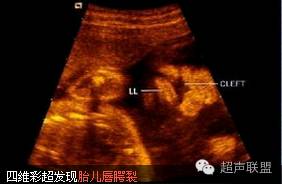

超声检查:最佳检查孕周为28周左右,羊水衬托好,从纵、横及冠状切面连续动态扫查,观察可见到唇弓回声中断,呈分又征,根据发生侧别和程度可有不同表现。合并腭裂时于门齿后方融合不全,造成腭开放,鼻腔相通,此时上唇结构消失,鼻小、向健侧移位,患侧鼻翼内陷。两鼻孔距离增大,或仅见一鼻孔(严重腭裂时)。超声对唇裂的检出率国内报道达852%,产前诊断率根据胎儿大小、胎位和胎儿面部有无羊水衬托有关,诊断的经验性也很强。近年来开展的四维超声能够对胎儿面部进行立体成像,直接得出类似拍照片的立体效果,使面部病变一目了然,进一步提高了唇裂的检出率。

胎儿唇腭裂三维超声表现

所见唇裂典型者呈"^" "" 字形,轻者裂口断端无明显增厚,鼻外表形态正常,双鼻孔同等大小且对称;重者裂口断端厚薄不等,鼻外表形态失常,双鼻孔不对称且大小不一。

单侧完全唇裂伴牙槽突裂或完全腭裂,三维超声可见鼻唇外表形态严重失常,结构紊乱,鼻梁塌陷变形,上唇部分缺失,鼻唇间存在不规则孔洞,有时可见与鼻腔连为一体;

总结: 1.胎儿唇裂声像图改变 唇裂时,颜面部冠状切面上唇连续性中断,显示一侧或两侧缺损,口唇张开时裂隙更加明显,唇部可呈字形,与其上方鼻子构成形结构。当裂口达鼻孔时,提示为完全性唇裂。横断时上唇弧形光带连续性中断。

2.胎儿腭裂声像图改变 腭部位于口腔的顶部,其前方及两侧均有上颌骨牙槽突遮挡,限制了二维超声的扫查及显示,因此腭裂的诊断是产前超声诊断的难点。牙槽突裂的胎儿显示牙槽突的弧形强回声光带连续性中断,牙槽突裂合并其后方的硬腭裂时,可以显示硬腭裂隙的低回声影像,但是不合并牙槽突裂的硬腭裂通常难以发现,而胎儿软腭裂目前超声还不能做出诊断。三维超声检查通过对容积数据的后处理有时可以获得比二维超声更多的诊断信息,有利于腭裂的诊断。

超声检查中,一些假象易造成胎儿唇腭裂的误诊,包括:人中切迹、脐带压迹及扫查方位不当造成的回声失落等,因此应进行多角度多切面的观察。